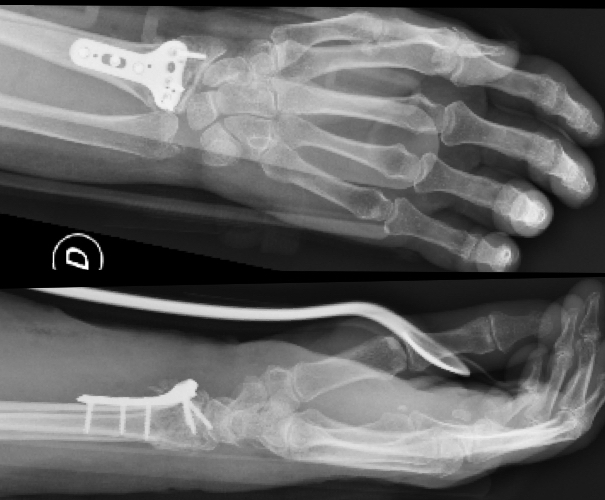

Wrist fractures Fay Pedler